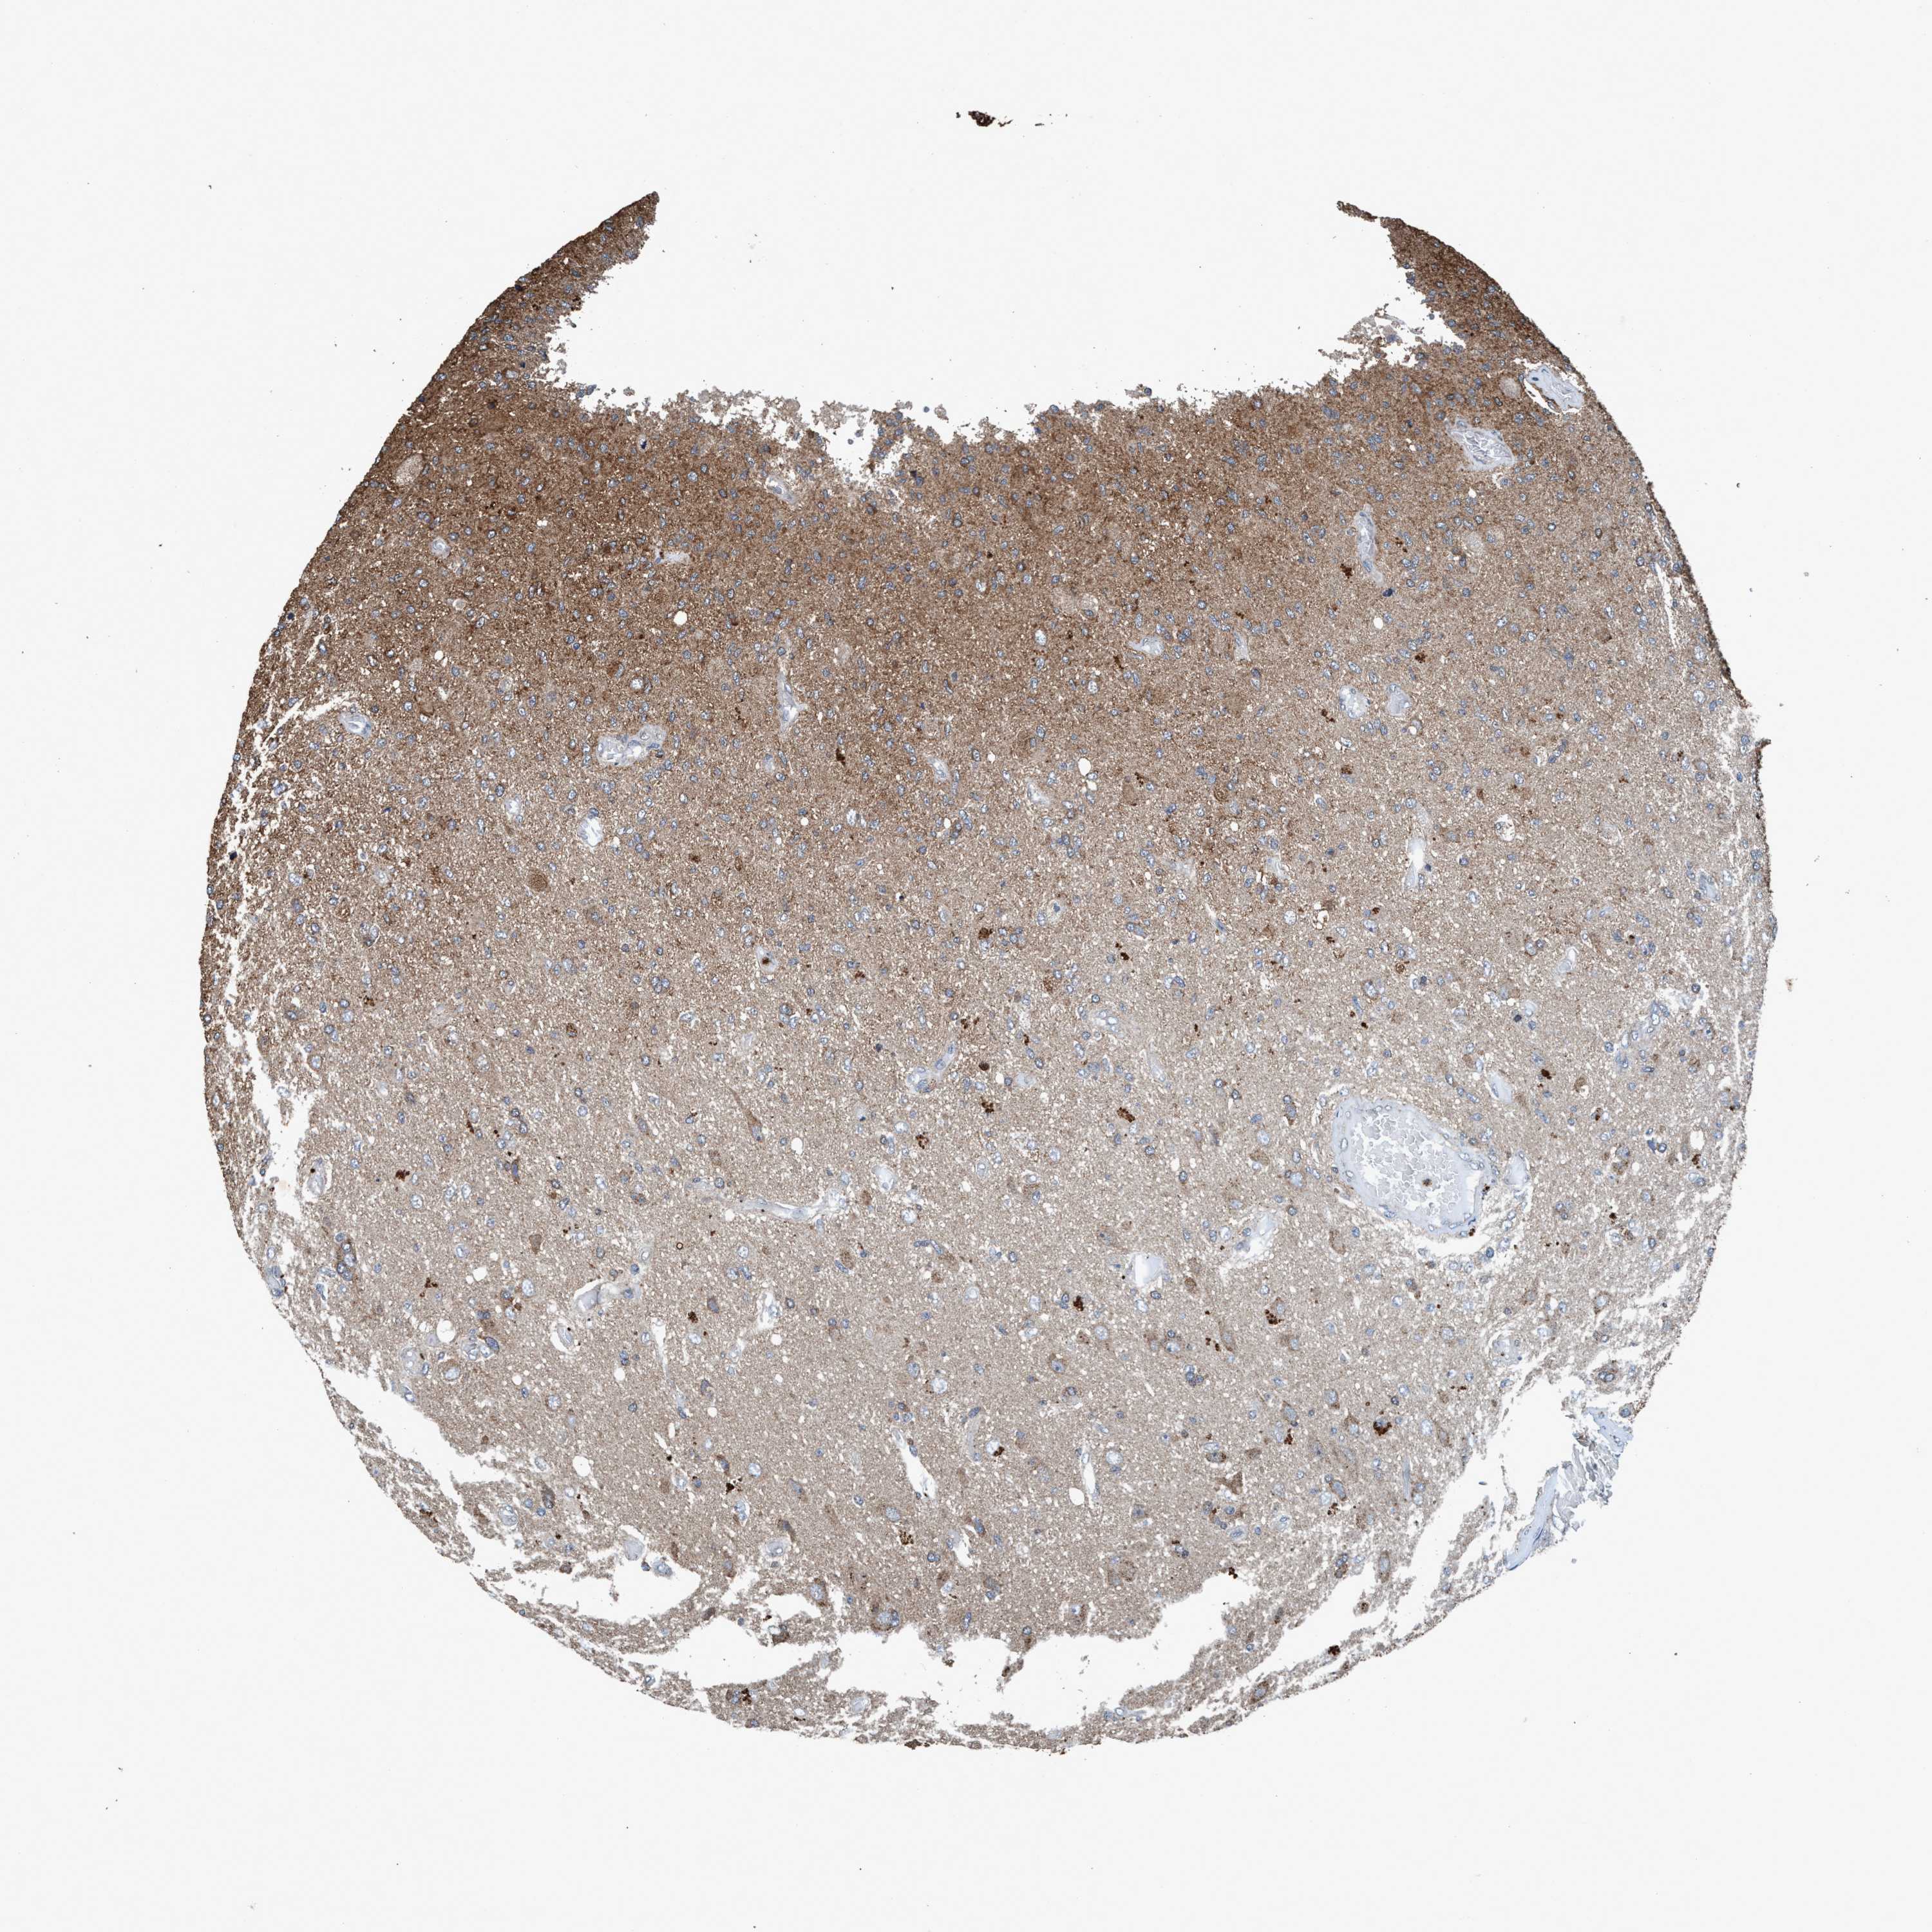

GLIOMA - Protein expressioni

A mouse-over function shows sample information and annotation data. Click on an image to view it in a full screen mode. Samples can be filtered based on level of antibody staining by selecting one or several of the following categories: high, medium, low and not detected. The assay and annotation is described here.

Note that samples used for immunohistochemistry by the Human Protein Atlas do not correspond to samples in the TCGA dataset.

Antibody stainingi

Antibody staining in the annotated cell types in the current human tissue is reported as not detected, low, medium, or high, based on conventional immunohistochemistry profiling in selected tissues. This score is based on the combination of the staining intensity and fraction of stained cells.

Each image is clickable and will lead to virtual microscopy that enables deeper exploration of all samples and also displays staining intensity scores, fraction scores and subcellular localization as well as patient and tissue information for each sample.

Antibody HPA064427

Antibody HPA075510

Antibody CAB021903

Staining

High

Medium

Low

Not detected

Intensity

Strong

Moderate

Weak

Negative

Quantity

>75%

75%-25%

<25%

None

Location

Nuclear

Cytoplasmic/membranous

Cytoplasmic/membranous,nuclear

Glioma, malignant, Low grade

Glioma, malignant, High grade